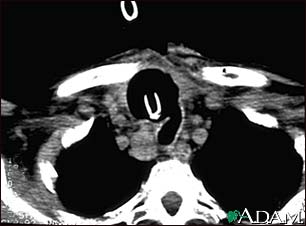

Thyroid cancer - CT scan

This CT scan of the upper chest (thorax) shows a malignant thyroid tumor (cancer). The dark area around the trachea (marked by the white U-shaped tip of the respiratory tube) is an area where normal tissue has been eroded and died (necrosis) as a result of tumor growth.